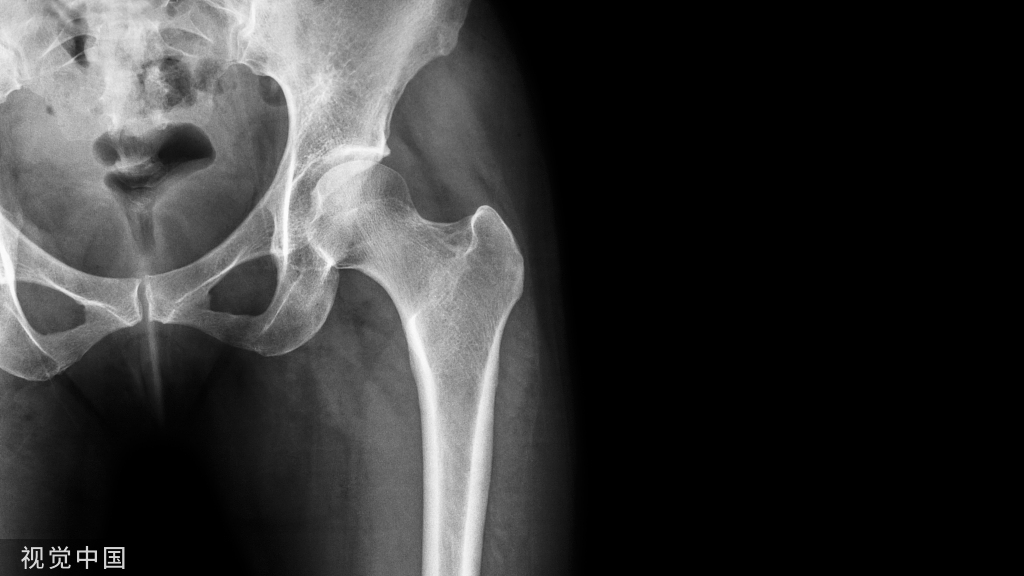

股骨髓内钉应该是创伤医生的拿手绝活了,以微创的方法完成一个完美的固定。今天分享一些股骨髓内钉的手术技巧,这些可都是吃线吃出来的,注意收藏哦。

总结:随着髓内钉设计的进步,医生们已经可以用髓内钉治疗股骨近端、中段、远端、各种复杂的股骨骨折了,很多老外在开会时都把自己叫一个nailer,就是只用髓内钉!

练好髓内钉技术,做一个牛X的创伤大夫